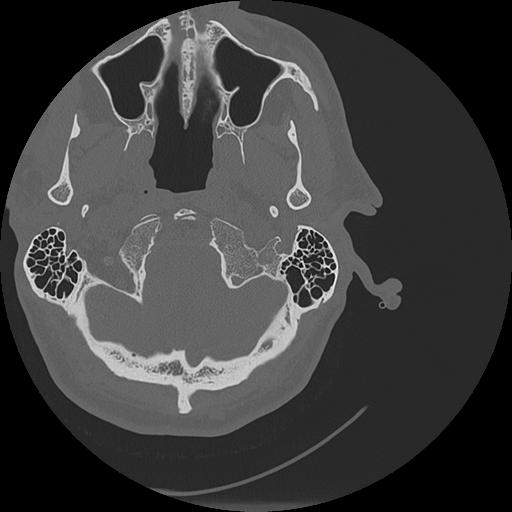

7 HUESO,,Vol,0.5,HUESO,,